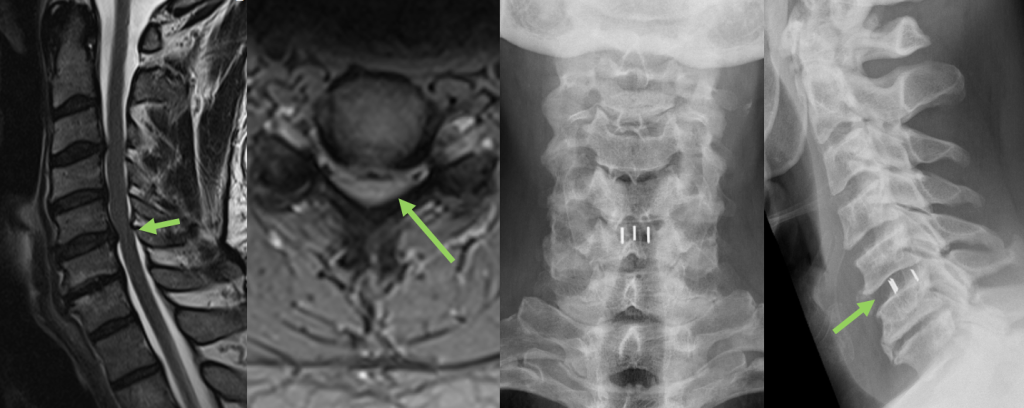

Zervikaler/Lumbaler Bandscheibenvorfall

Im Rahmen degenerativer Verschleißprozesse der Bandscheibe kann es zum Austritt von Bandscheibengewebe in den Wirbelkanal kommen. Durch Bedrängung der dort verlaufenden Nerven kommt es abhängig von der Schädigungshöhe zu Schmerzen, Taubheitsgefühl und Lähmungserscheinungen im Bereich der Arme bzw. Beine. Wird das Rückenmark selbst durch den Druck der Bandscheibe geschädigt, so können Blasen-Mastdarmstörungen oder gar eine Querschnittlähmung auftreten.

Im Normalfall kann der lumbale Bandscheibenvorfall minimalinvasiv mit Hilfe des Mikroskops entfernt werden, ohne dass eine Stabilisierung der Wirbelsäule notwendig ist.

Beim zervikalen Bandscheibenvorfall wird in der Regel die Bandscheibe mit einem Platzhalter ersetzt, nachdem diese unter dem Mikroskop vollständig entfernt wird.